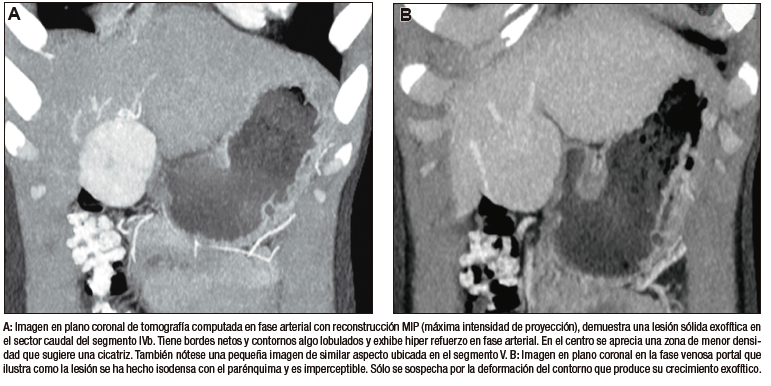

La HNF se manifiesta como uno o más nódulos (múltiple en aproximadamente 20%) de bordes netos y contornos lobulados. En la TCMC tiene densidad similar o apenas menor a la del parénquima adyacente. Si la cicatriz es visible (60%) en la TC es hipodensa. (Figura 3) En la RM su señal es isointensa o apenas hipo o hiperintensa en T1 e isointensa o un tanto hiperintensa en T2. (Figura 4) La cicatriz es hiperintensa en T2 (visible 80% en la RM), característica clave para diferenciarla del hepatocarcinoma fibrolamelar (cuya cicatriz es hipointensa en T2 por fibrosis o por calcificación). Por otra parte, en algunos casos la diferenciación puede ser difícil ya que ambas son lesiones que ocurren en pacientes jóvenes con hígado sano y presentan similar aspecto y comportamiento poscontraste. Típicamente, la lesión realza intensamente en la fase arterial en forma homogénea y su densidad (o intensidad de señal en la RM) disminuye en fases sucesivas pero suele persistir levemente reforzada con respecto al hígado.4, 5 Los hepatocitos que forman la HNF son positivos para las proteínas transportadoras, característica que, sumada a la presencia de conductos biliares, explican el refuerzo de estas lesiones en la fase hepatobiliar en la RM con empleo de contraste hepatoespecífico. Esto permite establecer el diagnostico con un alto grado de certeza y alejar (sin descartar absolutamente) la posibilidad de un adenoma hepatocelular. El refuerzo puede ser isointenso con el parénquima, difusamente hiperintenso e hiperintenso en la periferia. (Figura 5) Dada la naturaleza benigna de la lesión, carece de riesgo de malignidad y el manejo de la HNF es conservador.8 Si el diagnóstico por imágenes es firme, no se requiere seguimiento. Si la lesión es sintomática, presenta características no típicas, es pediculada o exofítica, el caso debería ser sometido a discusión por un equipo multidisciplinario. La indicación de cirugía por la HNF es excepcional en casos sintomáticos o en raras circunstancias como sangrado o rotura.

Figura 3. HNF en la tomografía computada